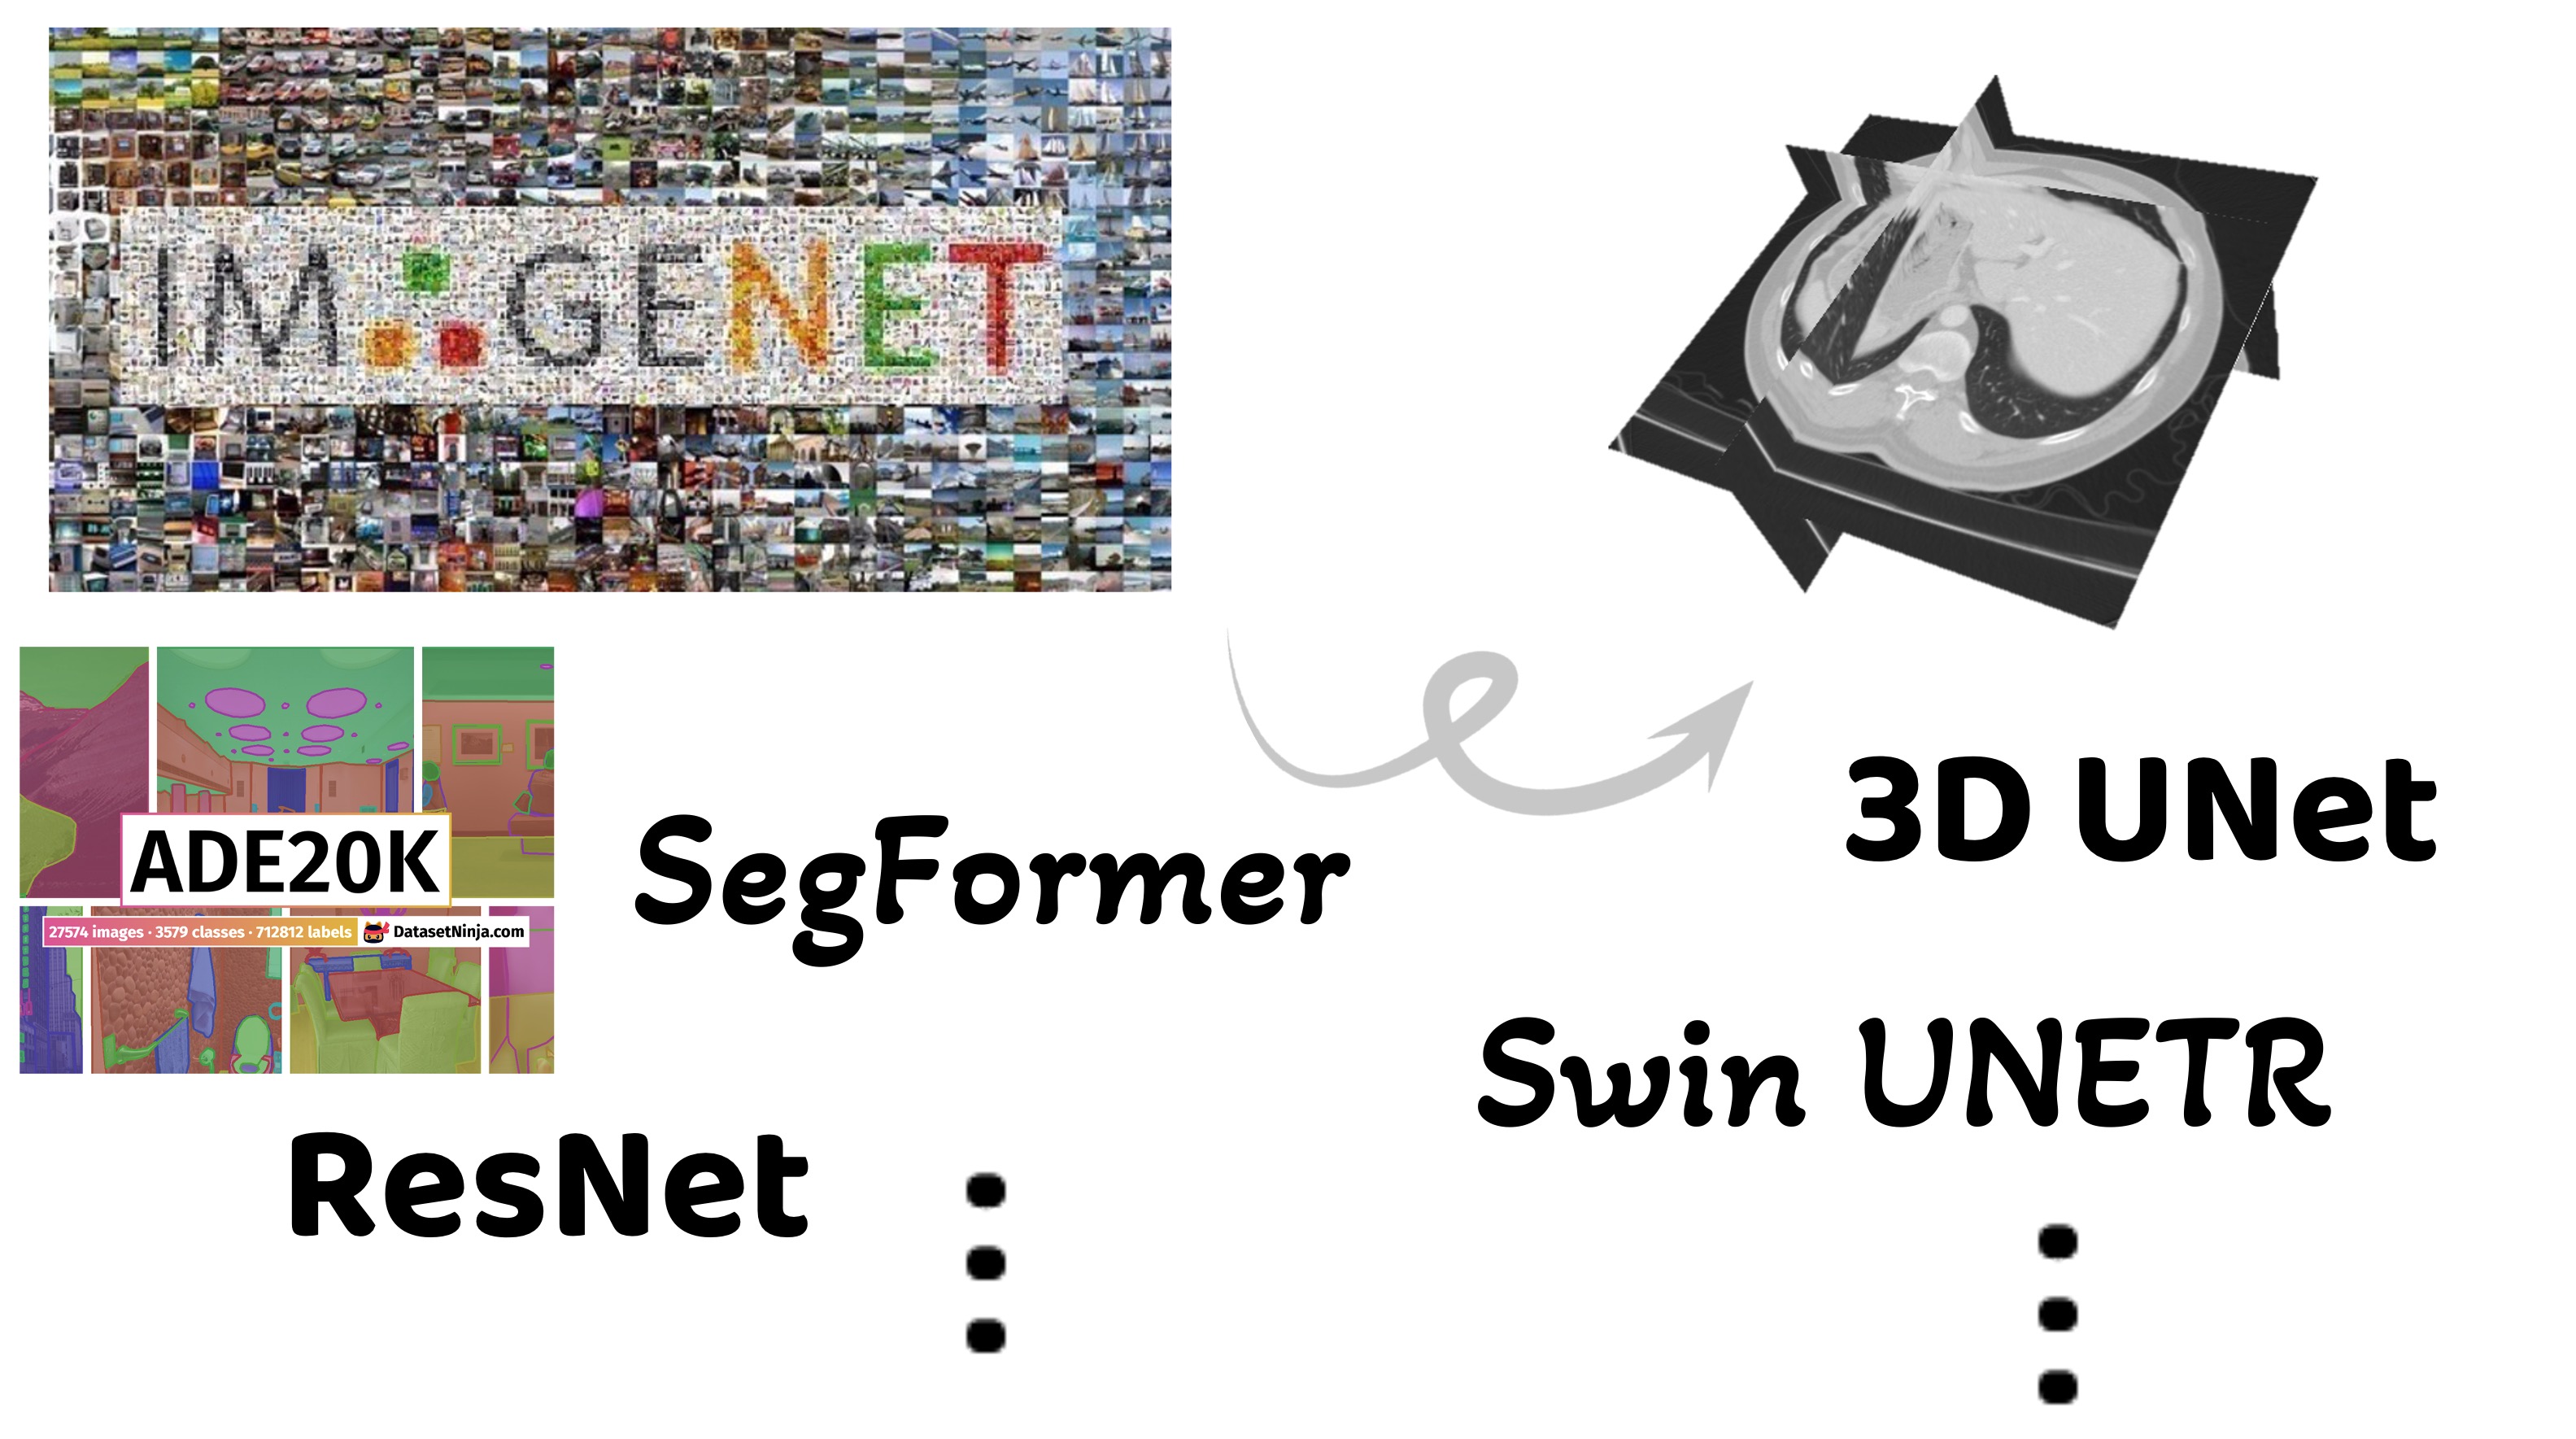

Semi-supervised 3D Medical Segmentation from 2D Natural Images Pretrained Model

Lecture Notes in Computer Science

·

01 Jan 2026

·

doi:10.1007/978-3-032-09513-8_6